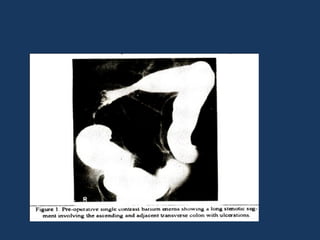

• Fig : marked

spiculations in the asc

colon,caecum and

terminal ileum

Stage 2 • Ulcerations •Fig : marked spiculations in the asc colon,caecum and terminal ileum